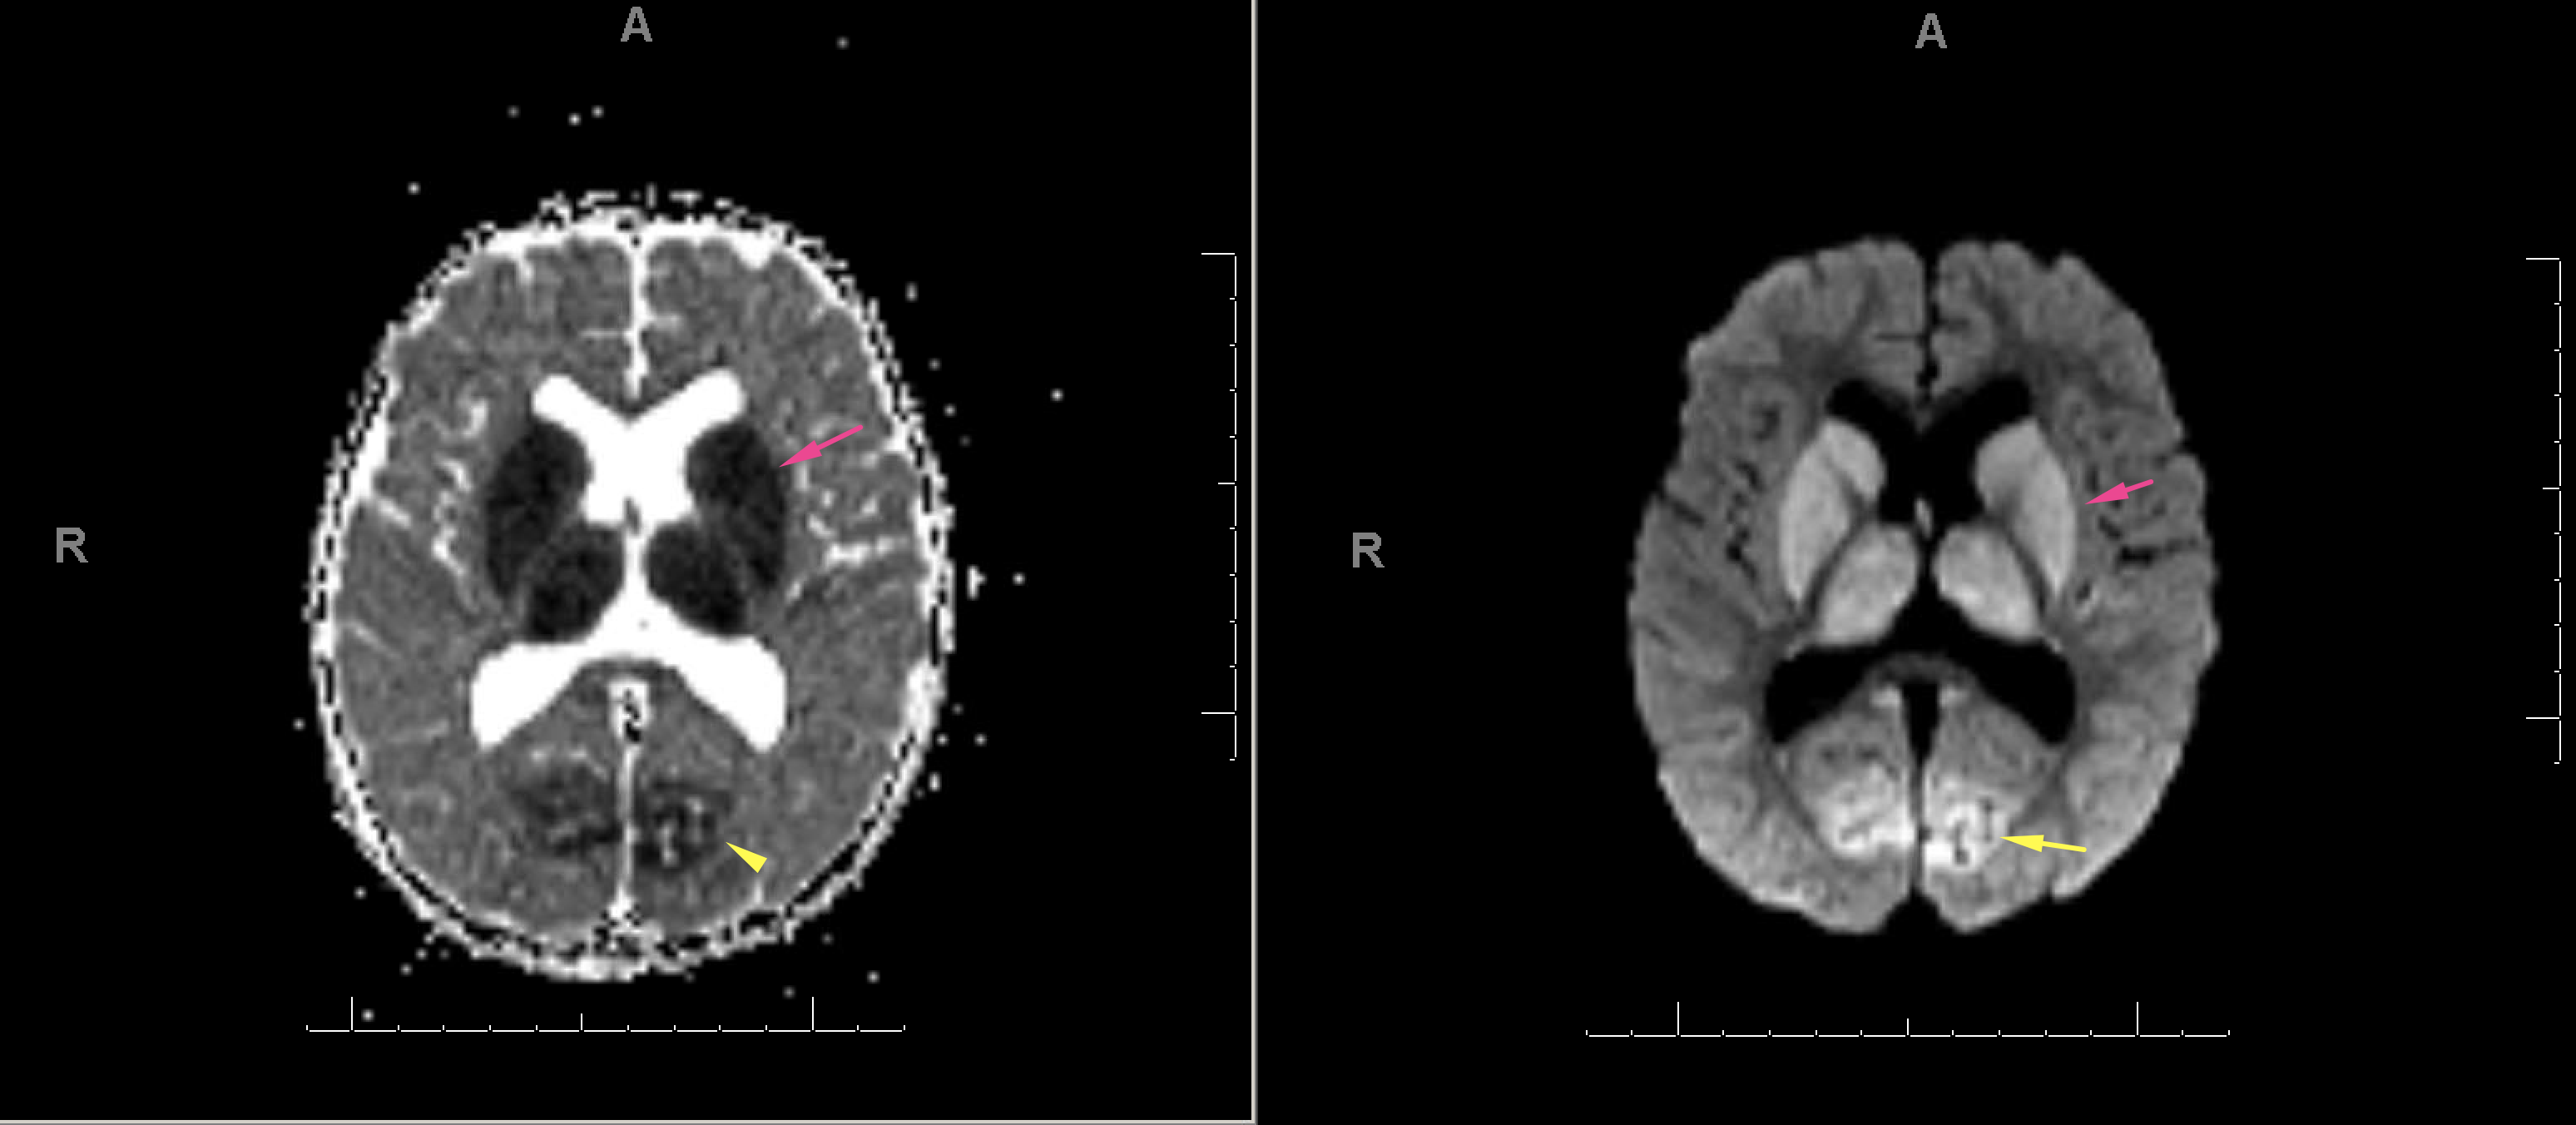

Indication: Trauma, evaluate for brain death

Radiotracer: Tc99m ECD

Sample ReportBrain perfusion is present in the bilateral cerebral cortex and cerebellum. These findings are not consistent with brain death.